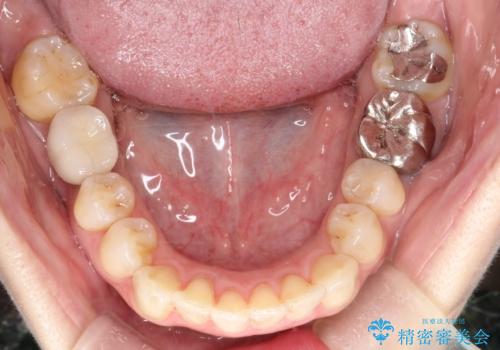

- 前歯のがたつきを主訴に来院されました。

なるべく目立たない矯正をご希望されたので、インビザラインにて治療することとなりました。